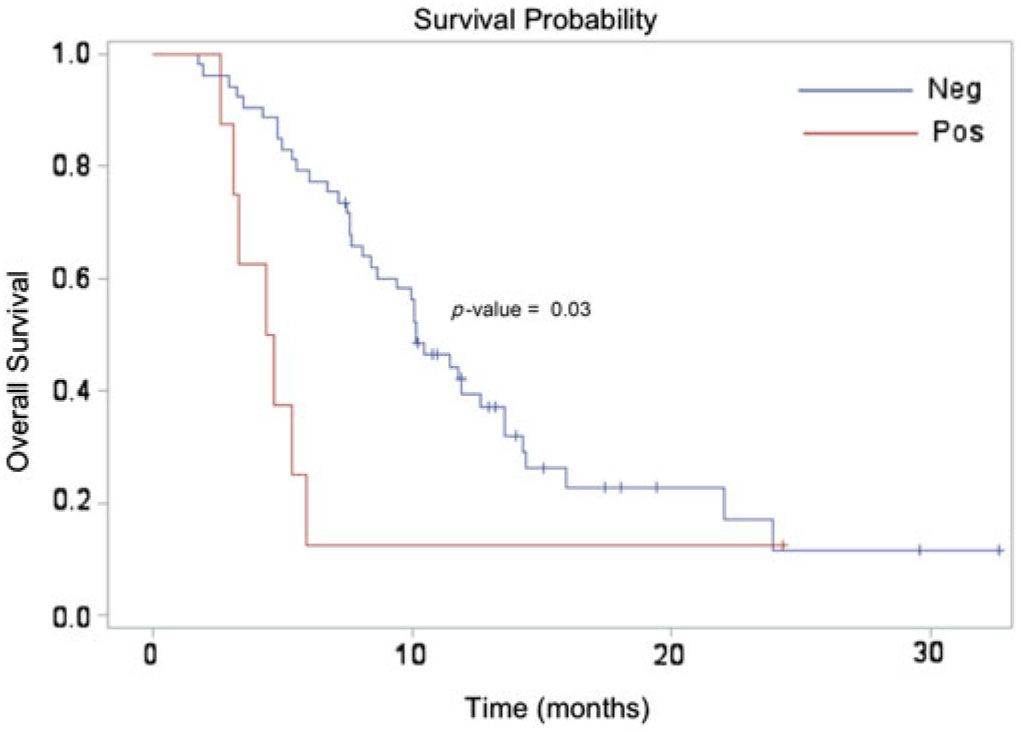

The median survival for the entire cohort was approximately 10 months, which is slightly higher than what has been reported in the literature for those with suspected recurrent high-grade glioma (3–6 months).Reference Fatterpekar, Galheigo, Narayana, Johnson and Knopp Reference Fatterpekar, Galheigo, Narayana, Johnson and Knopp28 This unexpected finding may be related to our case selection, as we only included patients who received DSC-MRP – which, at our institution, are only those well enough to be considered for salvage therapy. Median survival for patients with a positive DSC-MRP scan (4.5 months) was significantly lower compared to those with a negative DSC-MRP scan (10.2 months), [hazard ratio (HR) = 2.51; 95% confidence interval (CI) = 1.10–5.67; p = 0.03]. (Figure 2) The adjusted analysis including all pre-selected variables (age, gender, KPS, tumor grade, extent of surgical resection) demonstrated a similarly significant relationship (HR = 2.53, 95% CI: 1.05–6.14; p = 0.04).

Figure 2. Kaplan Meier survival estimate demonstrating a significant difference between the perfusion-negative (median survival 10.2 months) and perfusion-positive (median survival 4.5 months) cohorts.